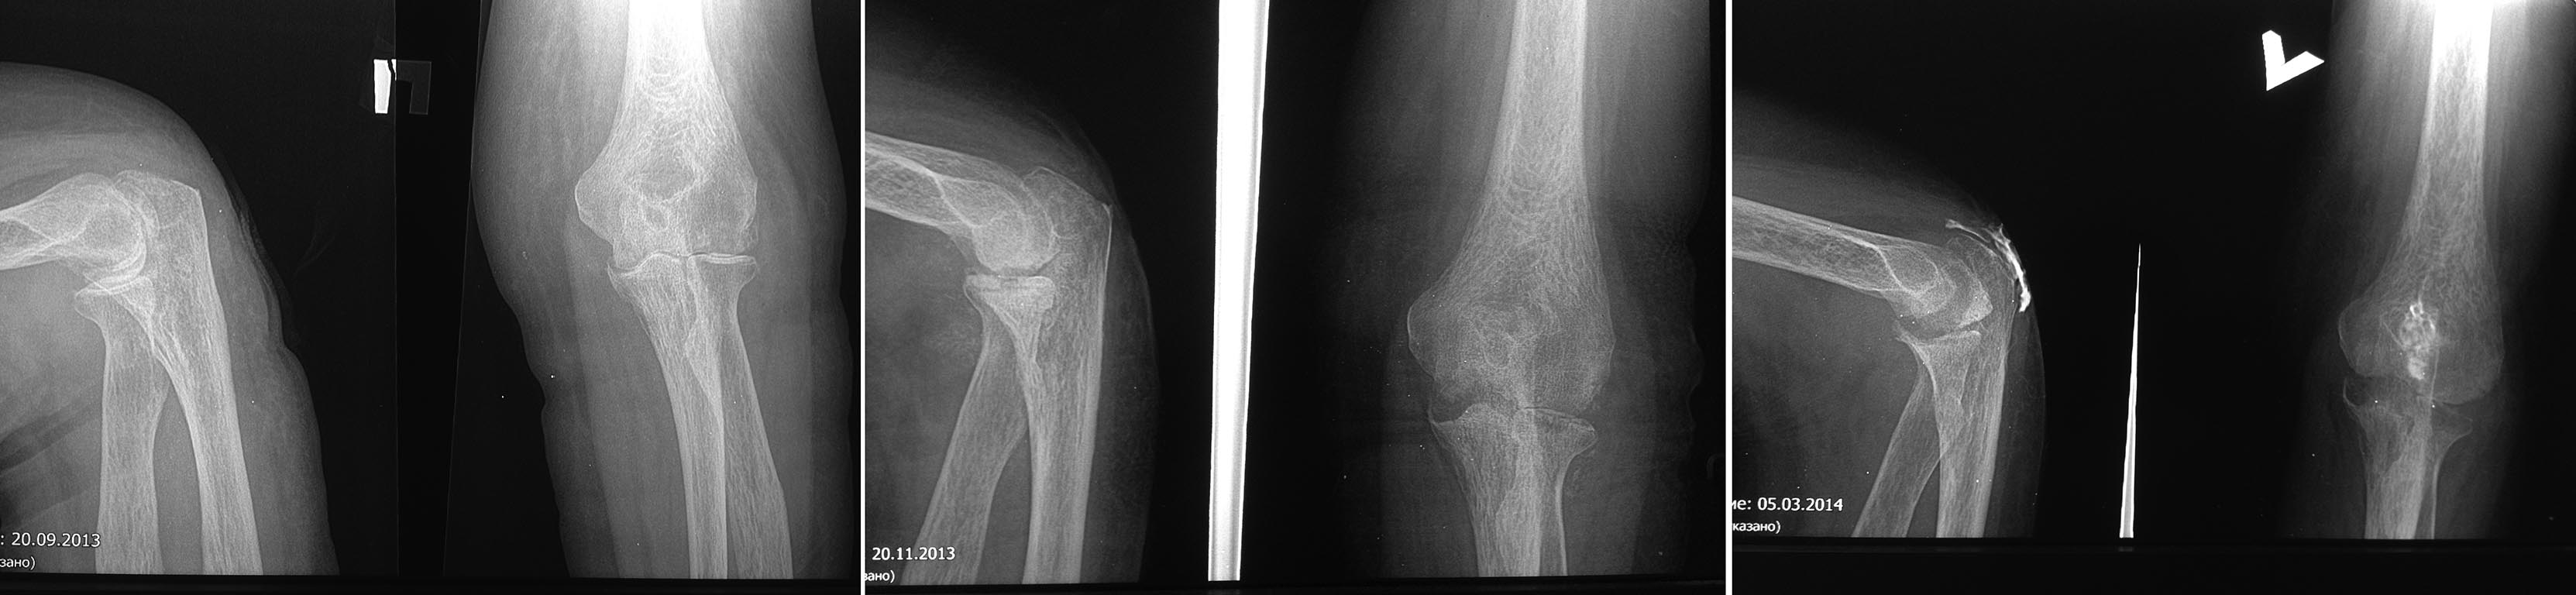

В феврале 2014 находилась на стац. лечении в травм. отд. обл. б-цы где выполнялась: Ревизия и иссечение свища области левого локтевого отростка, удаление экзостоза локтевого отростка. К моменту заживления п/о раны, перед выпиской – рецидив заболевания, повторно открылся свищ, появилось гнойное отделяемое. Не смотря на это, выписана из травм отделения, направлена на амбулаторное лечение по месту жительства. Наблюдалась у хирурга поликлиники ЦРБ, выполнялись перевязки – без положительной динамики. В настоящее время в очередной раз получает стационарное лечение в ХО ЦРБ, получает антибактериальную терапию, перевязки.

В проекции локтевого отростка по рубец, центре п/о рубца свищ диаметром 0,3 см, из свища гнойное отделяемое. Движения в локтевом суставе активные - качательные, в пределах 5-10о, пассивные 30-80о. МРТ нет. Только платно в областном центре, больная себе позволить не может.

Возможно, я не дооцениваю ситуацию, но, исходя из результатов фистулографии (снимки, как на меня, достаточно информативны и качественны) сустав не вовлечен в очаг воспаления, и его раскрытие при ревизии было бы большой ошибкой в плане прогностической диссеминации возбудителя инфекции

Доброго времени суток. Уважаемые коллеги, соглашусь с Олегом Шепетой в том, что "Возможно, я не дооцениваю ситуацию" (с). На рентгенограммах явные признаки деструкции суставных концов костей. И то, что контраст не доходит до полости сустава не должно быть определяющим тактику фактором.